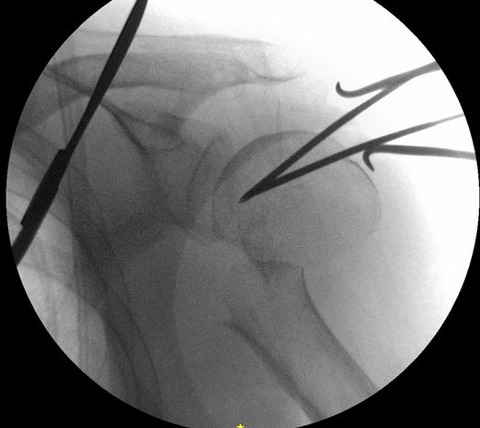

髄内釘のエントリーポイントを至適にするためには、転位した上腕骨頭を整復する必要があります。私は2.4 K-wireを肩峰外側から上腕骨頭に2本刺入して、これをjoy-stickにして整復します。

まず、1本目の2.4 K-wireを肩峰下に沿ってできるだけ上腕骨頭内側に進めます。この際、どうしても肩峰の外側が邪魔になるのですが、ある程度仕方ありません。

1本目の2.4 K-wireをできるだけ上腕骨頭内側に刺入して、これをjoy-stickにして整復します。しかし1本では整復力が弱いので2本目を刺入して、更に強力に整復を行います。

2本のK-wireをjoy-stickにして思いっきり整復します。上腕骨頭を内転位に保ちながら、上腕骨頭の頂点からガイドワイヤーを刺入します。

K-wireで上腕骨頭を内転位に整復位を保っておかないと腱板に牽引されて外転転位してしまい、髄内釘のエントリーポイントがかなり大結節寄りになってしまいます。

髄内釘のエントリーポイントが大結節寄りになりすぎると、ネイル挿入時に骨折を併発したり、髄内釘の固定力が落ちるので注意が必要です。この手術で一番重要なポイントだと思います。